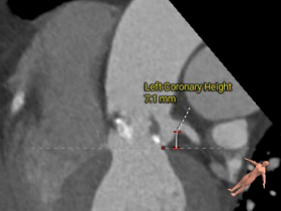

左冠开口高度:7.1mm

右冠开口高度:13.7mm

左窦瓣叶长度:15.2mm

右窦瓣叶长度:16.6mm

• 左冠开口高度低、瓣叶长,建议球囊预扩评估冠脉风险;右冠开口高度可、瓣叶长度可、窦宽相对瓣膜可 ;综合评估冠脉风险低;